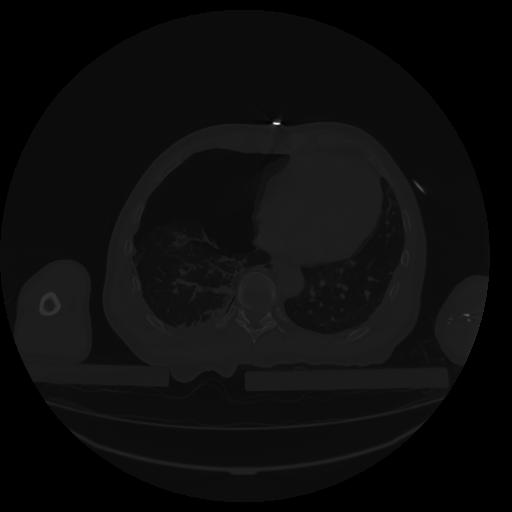

34 CUERPO,CE,Vol,1.0,CUERPO,,